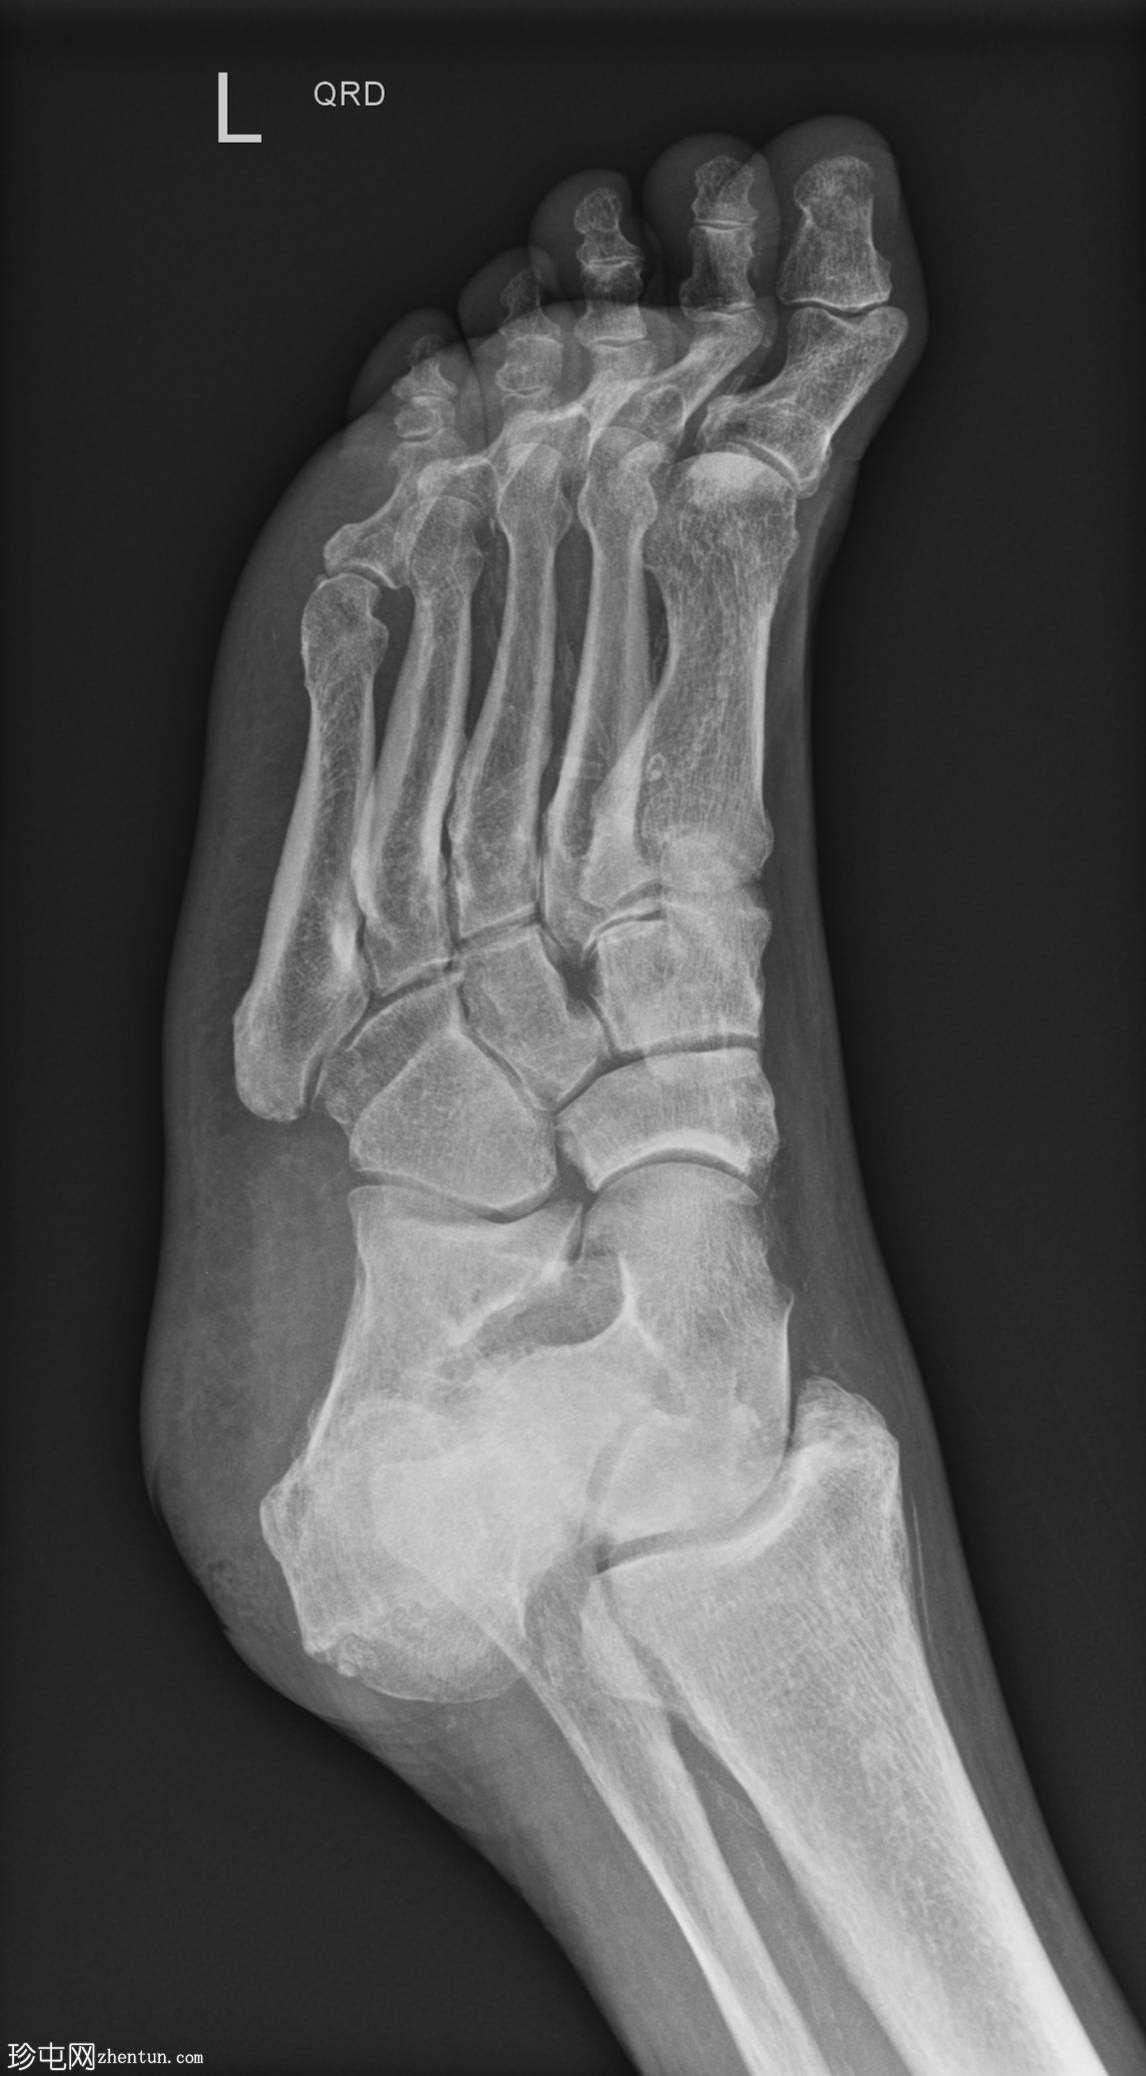

X光片

斜位片

跖趾关节爪状趾畸形

动脉钙化

爪状趾畸形是指小趾跖趾关节过度伸展,导致近端指间关节(PIP)和远端指间关节(DIP)屈曲。